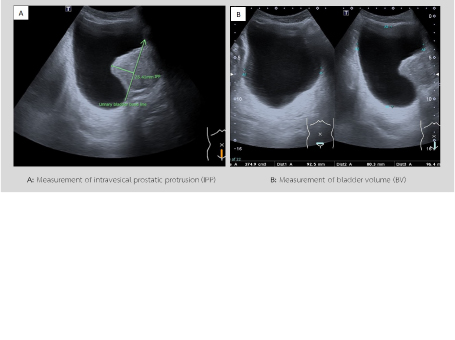

• The study of relationships between bladder volume and intravesical prostatic protrusion on transabdominal ultrasound in patients with benign prostatic hyperplasia

Watinee Suwankesa, M.D.

7-22